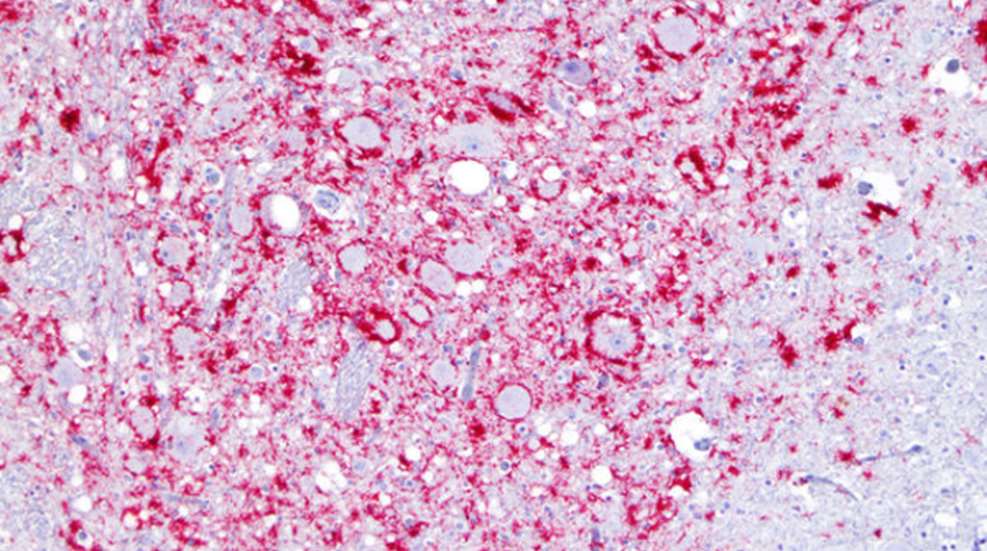

LADDL received a grant of more than $380,000 entitled “Increase Capacity for Testing for Chronic Wasting Disease (CWD)” from the National Animal Health Laboratory Network (NAHLN) USDA Farm Bill for 2022. The purpose of this grant from NAHLN is to increase the CWD testing capacity in Louisiana. In the event CWD is detected in Louisiana, regional sampling rates will be dramatically expanded in an effort to determine prevalence of the disease in the affected area. Statewide CWD surveillance will increase as well. The NAHLN USDA Farm Bill funding will be used to expand LADDL’s immunohistochemistry (IHC) testing capabilities through automation and additional equipment for IHC staining to accommodate future CWD testing needs of LDWF.

The LDWF and LADDL have a joint interest in diseases that affect white-tailed deer, including CWD. Samples are collected from hunter-harvested deer and target deer, including symptomatic deer and pen escapes. The samples are then sent to LADDL for testing. This current USDA Farm Bill grant will allow LADDL to upgrade its prior system for CWD-testing so that it can more than triple CWD surveillance testing capacity and efficiency in Louisiana.